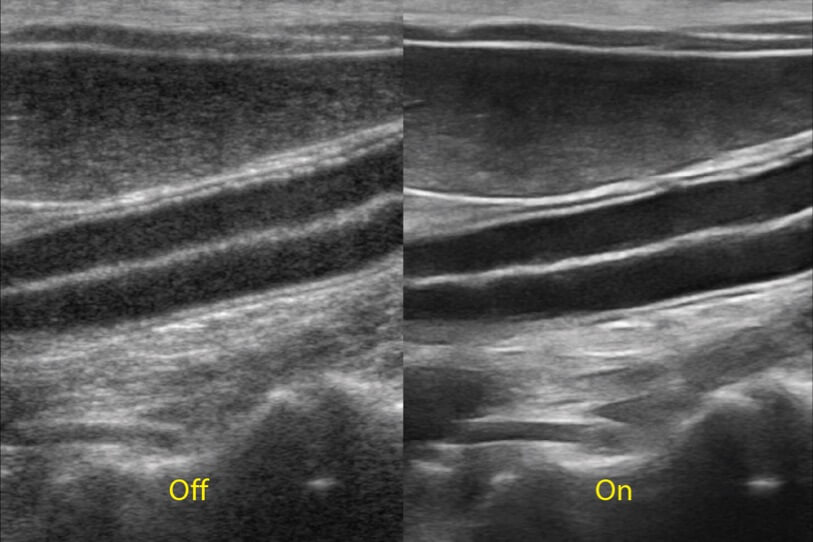

增強(qiáng)穿刺針在動(dòng)物解剖結(jié)構(gòu)中的位置,提高穿刺介入的安全性和準(zhǔn)確性。